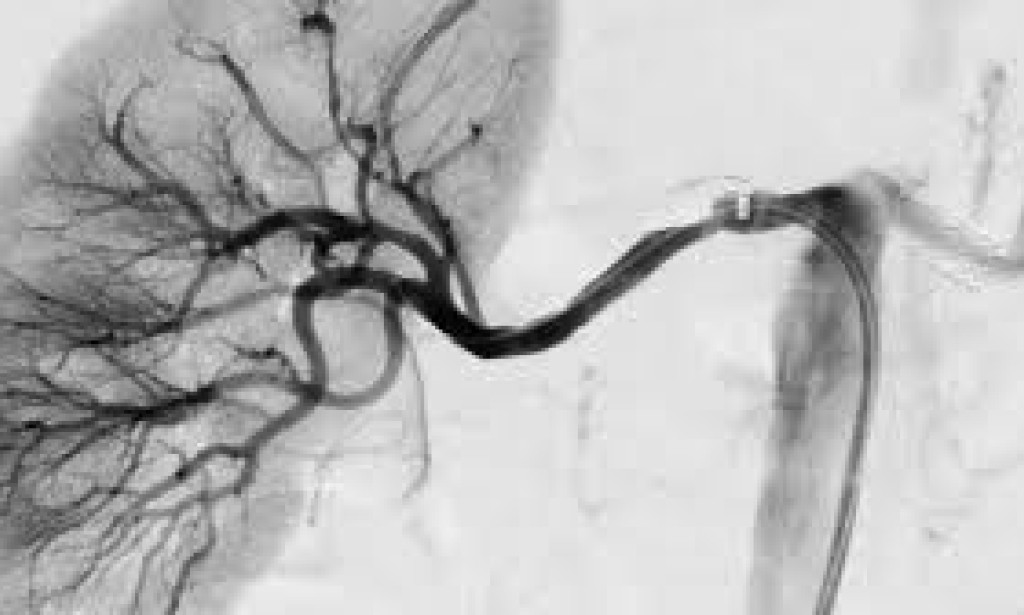

Hypertension, or high blood pressure, is another leading cause of kidney failure. When blood pressure remains consistently high, it can damage the blood vessels in the kidneys, reducing their ability to filter waste and maintain fluid balance. This condition, called hypertensive nephropathy, can lead to kidney failure over time.

Dr. David Miller, a cardiologist, notes, "Chronic high blood pressure can cause the arteries in the kidneys to narrow, weaken, or harden, making it difficult for the kidneys to effectively filter waste. This ultimately leads to kidney damage."